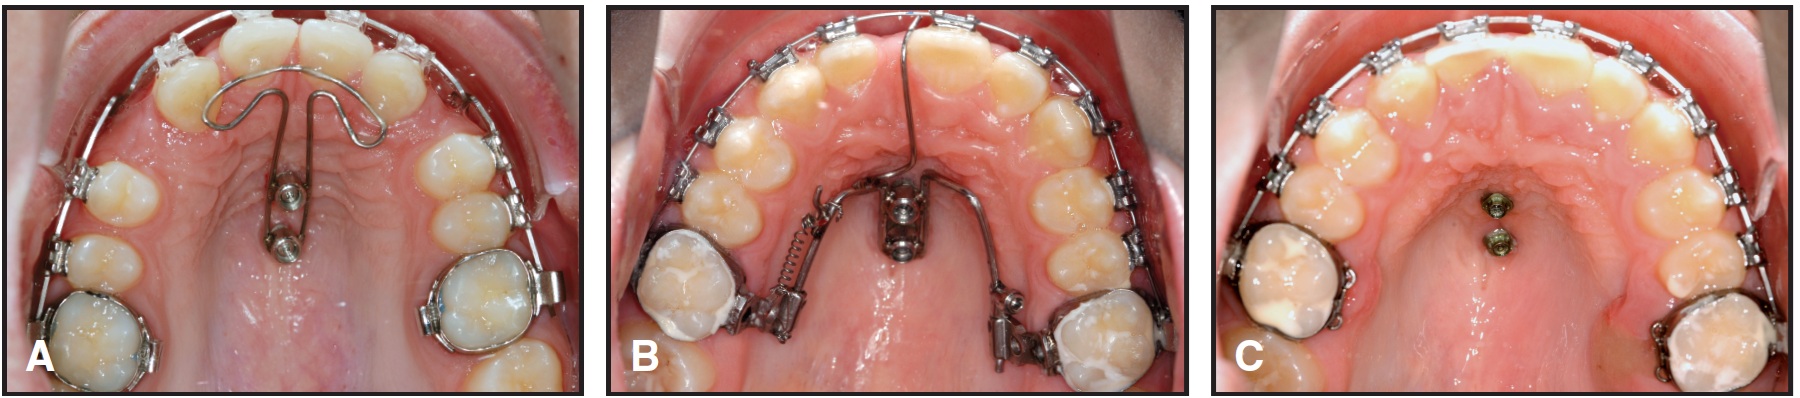

Fig. 4 Maxillary molar distalization with Beneslider. A. Patient before distalization. B. Class I molar relationship established after seven months of distalization (amount of distalization indicated by length of wire extending distal to molar tube). C. Superimposition of pre- and post-treatment cephalometric tracings shows bodily movement of first molars, due to direction of force through molar's center of resistance.

Fig. 6 Skeletal anchorage of maxillary molars for retraction of anterior teeth. A. Abutment with .032" wire used with Mobile Intraoral Arch system. B. Additional transverse posterior wire welded to prevent arch expansion.

Fig. 10 Uprighting and distalization of maxillary right first molar with 2mm x 11mm Benefit mini-implant and bracket abutment. A. Segmental .017" x .025" stainless steel wire, ligated to bracket abutment, acts as lever arm; power chain provides uprighting and distalizing force. B. Sufficient space gained after three months for eruption of maxillary right second premolar.